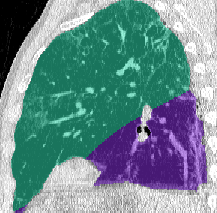

Lung segmentation results for the polymorphic and nonpolymorphic models are shown in Figure 3. Quantitative evaluation of lung segmentations was performed on CT images by comparing the segmentations to ground truth manual segmentations. The Dice coefficient was used to measure volume overlap and the average symmetric surface distance (ASSD) was used to assess boundary accuracy. The ASSD and Dice coefficient results for each of the four evaluation datasets are shown in Table 2. Overall, on the COVID-19 dataset the polymorphic model achieved an average ASSD of mm and average Dice coefficient of . By comparison, the nonpolymorphic model achieved an average ASSD of mm and average Dice coefficient of . ASSD and Dice coefficient results with respect to nonaerated lung volume fraction are displayed in Figure 4. Two-way analysis of variance revealed a significant interaction between model and nonaerated fraction for each evaluation metric, indicating that the regression coefficients with respect to nonaerated fraction were significantly different for polymorphic vs. nonpolymorphic models.

Lobar Segmentation

Lobar segmentation results for the proposed method and PTK are shown in Figure 5 for right lungs and Figure 6 for left lungs. For each image in the COVID-19 dataset (133 images in total), the lobar segmentation result was used to extract the amount of poor aeration () and consolidation () in each lobe. Common phenotypes of COVID-19 affected lungs were identified by hierarchical clustering over the fraction of poorly aerated and consolidated tissue in each lobe. Dendrographic analysis in Figure 7 reveals four primary clusters of patients that were identified by the hierarchical clustering: (a) mild loss of aeration primarily in the two lower lobes without consolidation; (b) moderate loss of aeration focused in the two lower lobes with or without consolidation in lower lobes; (c) severe loss of aeration throughout all lobes with or without consolidation; and (d) severe loss of aeration and consolidation throughout all lobes.